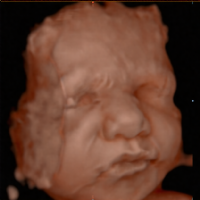

The ultimate in affordable 2D/3D/4D/HD non-diagnostic ultrasounds for expectant mothers. Genders less than $100. Viewing as early as 10-weeks. Family centered environment. 8K available. High ratings.